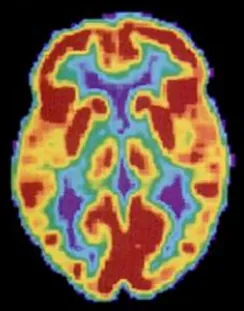

Pozytonowa tomografia emisyjna (ang. positron emission tomography (PET)) tworzy obrazy żywego, aktywnego mózgu (Ilustracja 3.27). Osoba poddawana takiemu badaniu najpierw wypija (albo wstrzykuje się jej) płyn z nieznacznie radioaktywną substancją, tzw. znacznikiem. Gdy znacznik znajdzie się w krwiobiegu, można monitorować jego ilość w dowolnym obszarze mózgu. Wiadomo, że wzrost aktywności obszaru mózgu powoduje wzrost przepływu krwi przez ten obszar, a więc i wzrost stężenia znacznika. Komputer pozwala rejestrować ruchy znacznika i tworzy mapę aktywnych i nieaktywnych obszarów mózgu podczas określonego zachowania. Obrazy PET nie są zbyt szczegółowe, nie pozwalają na dokładne zobrazowanie aktywności w czasie i są związane z narażeniem mózgu na promieniowanie. Dlatego technikę tę zastępuje się obrazowaniem czynnościowym rezonansem magnetycznym (fMRI). Jednakże w połączeniu z tomografią komputerową badanie PET wciąż jest wykorzystywane w niektórych sytuacjach. Techniki TK/PET pozwalają np. lepiej zobrazować aktywność receptorów neuroprzekaźnika i otwierają nowe możliwości w badaniach nad schizofrenią. Hybrydowa technologia TK/PET to szczegółowy obraz struktur mózgu (TK) i jego aktywności (PET).

Technika PET umożliwia zobrazowanie aktywności mózgu.

Ilustracja 3.27 Obraz PET ujawnia aktywność różnych obszarów mózgu. (Źródło: Departament Zdrowia i Opieki Społecznej, Narodowy Instytut Zdrowia)